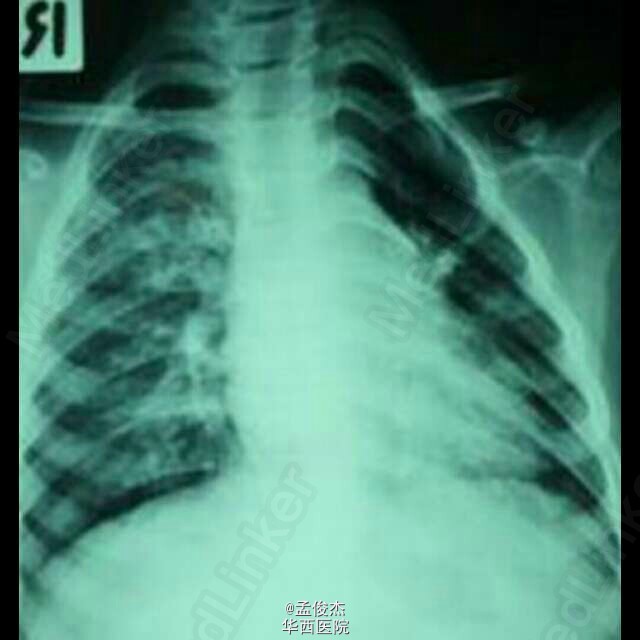

患儿6岁, 8天前患儿因咳嗽和轻度发热在当地医院就诊,使用抗组胺和化痰药无效,3天前天前出现面部红疹并扩散至躯干,遂至清迈医院就诊。入院后患儿持续发热至39.5℃和咳嗽加重,呼吸音减弱,全肺闻及湿罗音,并出现严重呼吸衰竭,呼吸过速40/分,心动过速110–120/分。诊断为麻疹病毒肺炎。给予 口服VitA (200 000 单位/天)2天;静滴阿米卡星(270 mg/天) 3天,头孢噻肟(2.8 g/天)7天。本例为曾经接种过麻疹病毒疫苗却出现重症肺炎的6岁男孩,典型的麻疹肺炎在出疹3日后消退,但是本例中患儿的症状的提示可能有细菌感染,需要用广谱抗生素。(来自medline)